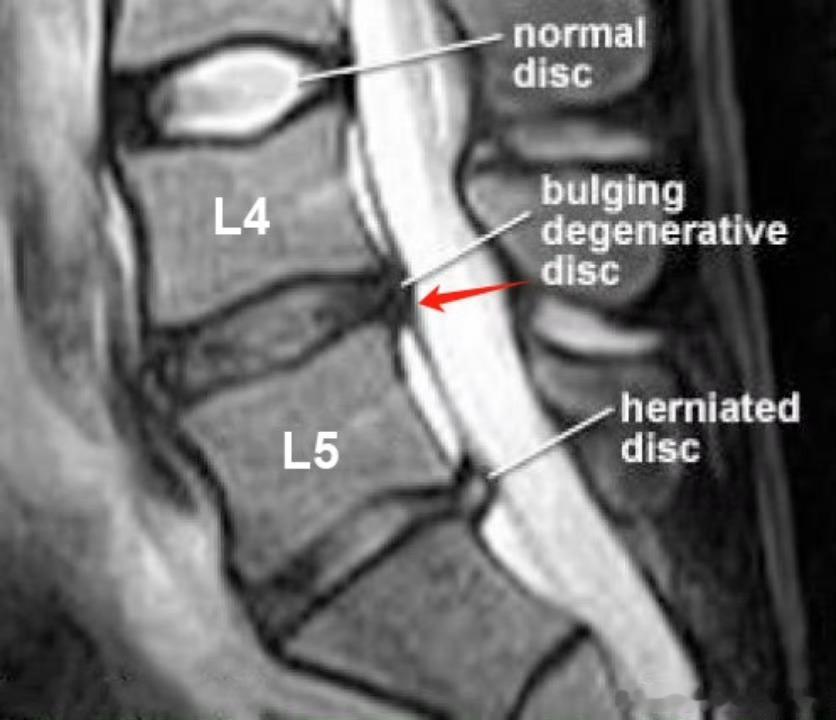

腰椎间盘突出 【腰突康复】继续来聊聊腰突,从基本的概念➕康复黄金法则➕康复误区:01.【椎间盘到底是什么】想象我们的脊椎骨像汉堡一样叠在一起,椎间盘就是中间的"缓冲垫"。它由两部分组成:✅外层纤维环:类似轮胎的坚韧结构✅内部髓核:类似果冻的凝胶物质当纤维环破裂导致髓核外流,压迫后方神经时,就会引发各种症状。02.【典型症状辨别】椎体中央刺痛:按压脊椎间隙时出现针扎样疼痛放射性窜麻:从臀部到脚底有过电般的放电感钝性疼痛:常见于小腿外侧/大腿内侧/臀部,易被误诊为肌肉损伤⚠️注意:单纯腰两侧或腰骶部疼痛,更可能是腰肌劳损、筋膜炎等问题03.【致病原因】椎间盘能承受600kg垂直压力,真正怕的是"剪切力":❌弯腰搬重物❌瘫坐姿势❌久坐不动的办公族❌髋关节灵活性差会加重腰椎代偿,增加发病风险04.【病情发展三阶段】膨出:纤维环未破裂(可逆)突出:纤维环部分破裂脱出:髓核完全流出(不可逆)提示:症状轻重与突出物压迫程度相关,有些人脱出无症状,有些人膨出却很痛苦。05.【康复黄金法则】急性期(水肿期)我们还是强调以静养为主,接下来我们重点讲解一些恢复期康复方案:✅肌肉松解:缓解腰背肌群紧张✅神经松动术:改善神经压迫症状✅核心强化:通过腹压训练稳定脊柱✅姿势矫正:恢复腰椎生理曲度06.【常见误区纠正】✘ 误区1:腰疼=椎间盘突出✓ 真相:需结合影像学+症状综合判断✘ 误区2:症状消失=痊愈✓ 真相:疼痛缓解只是炎症消退,结构损伤仍需持续康复✘ 误区3:不能做任何运动✓ 真相:科学锻炼可增强脊柱稳定性提醒:康复后建议每半年进行核心肌群评估,办公室人群建议使用人体工学椅+每小时起身活动。关于腰椎间盘突出,大家还有什么问题,可以在评论区留言腰突康复健闻登顶计划